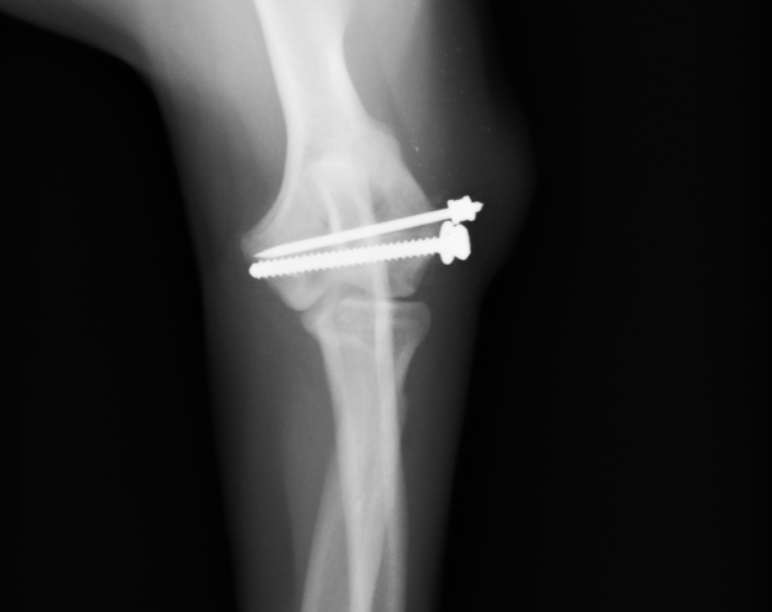

術後のX線画像です。ずれていた骨を太めのスクリューと、細いピンで固定しています。骨折線がわからないレベルまで固定できています。

術後2週間のレントゲン画像です。少し仮骨が出てきており、骨折線が分からなくなりました。この仮骨が減ってきたらインプラント抜去になります。